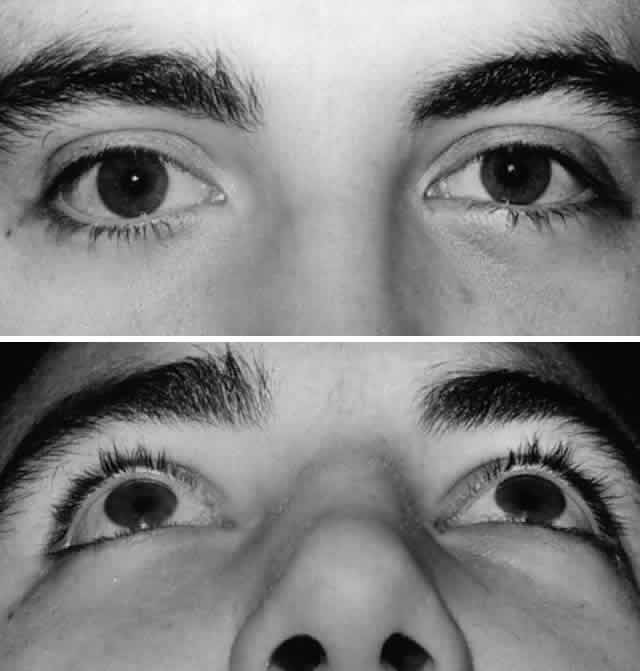

edema. The postoperative result is appreciated after resolution

of edema (Fig. 7).  Fig. 7. A. Postoperative appearance of patient in Figure 3 one month after left orbital blow-out fracture repair. B. Note good globe position with no evidence of enophthalmos. Ocular motility

returned to normal. Fig. 7. A. Postoperative appearance of patient in Figure 3 one month after left orbital blow-out fracture repair. B. Note good globe position with no evidence of enophthalmos. Ocular motility

returned to normal.

|